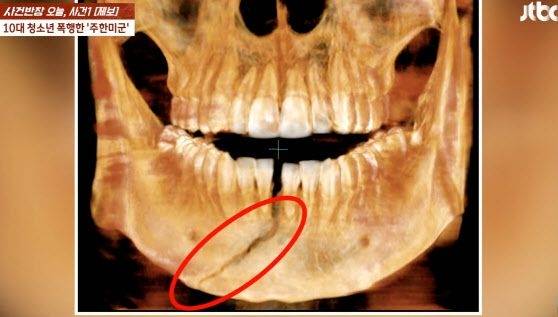

경기 평택에서 주한미군에게 맞아 턱뼈가 골절된 10대 남학생의 아버지가 "의사 말로는 죽지 않은 게 신기할 정도로 상처가 심하다"며 피해 사실을 알렸다.

![주한미군에 맞아 턱뼈가 골절된 10대 남학생의 엑스레이 사진.[사진 제공 = JTBC 사건반장 캡처]](https://img3.daumcdn.net/thumb/R658x0.q70/?fname=https://t1.daumcdn.net/news/202411/20/mk/20241120093002828jqyg.jpg)

A중사는 17일 0시 30분께 평택시 평택역 인근 한 거리에서 B(18)군의 얼굴을 주먹으로 때려 턱뼈가 부서지는 등 중상을 입게 한 혐의를 받고 있다. A중사는 190㎝의 키에 몸무게가 100㎏에 달하는 큰 체격으로 알려졌다.

B군 아버지는 19일 JTBC 사건반장을 통해 “의사한테 들은 내용은 ‘사람이 때렸다고 생각이 안 들었다’고 한다”며 “사람이 주먹으로 때렸을 때 관절이 이 정도 나가는 거는 성형외과 의사로 지내면서 처음 봤던 일(이라고 하더라)”이라고 전했다.

B군 아버지에 따르면 B군은 입안에 보철을 착용하고 고정한 상태로 8주간 있어야 하고, 평생 후유장애가 남을 수도 있다고 한다.